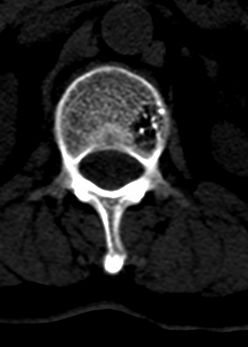

患者 女 54岁 外伤后检查发现l1椎体局部密度减低,请问这是什么病灶?

椎体内部局限性骨小梁稀疏、粗大改变,周围未见软组织肿块,首先考虑椎体血管瘤。